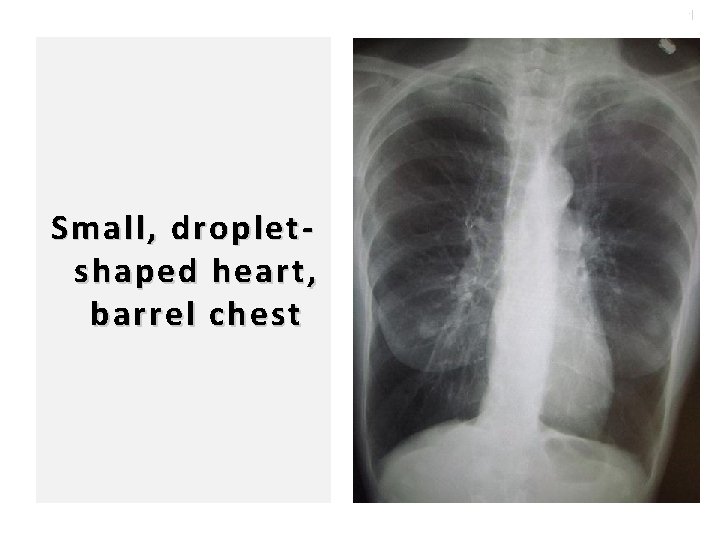

100 Small, dropletshaped heart, barrel chest

39 Features of severe disease �Anteroposterior diameter of the chest Barrel-shaped Chest Badgett RG, Tanaka DJ, Hunt DK, et al. Can moderate chronic obstructive pulmonary disease be diagnosed by historical and physical findings alone? Am J Med 1993; 94: 188.